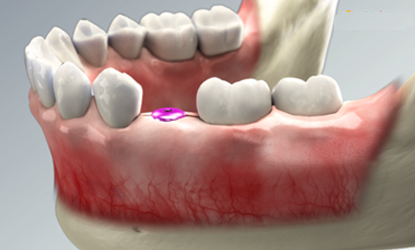

Implant process

Step 01

tooth extraction

tooth extraction